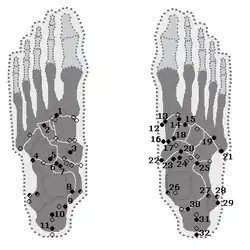

- Akzessorische Fußknochen

Insbesondere an den Fußwurzelknochen können eine Reihe von akzessorischen Fußwurzelknochen beobachtet werden. Sie sind teilweise weitverbreitet und in vielen Fällen symptomlos. Meist handelt es sich um Zufallsbefunde bei einer Röntgenuntersuchung. Das Os tibiale externum ist beispielsweise bei etwa einem Fünftel aller Erwachsenen vorhanden.[11] Das Os trigonum kommt bei 3–15 % der Erwachsenen vor.